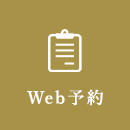

乳幼児の歯科健診の観察ポイント

顎顔面・顔貌・口腔機能の視診

- 骨格や顎骨の偏位、口唇閉鎖、舌の動きや位置などを診察しています。

歯垢付着状況の視診

- 判定部位・基準により診察しています。

乳歯の萌出状況 歯の形態・歯数の視診

- 乳歯の萌出状況を見ながら、歯の形態や歯数に異常がないか診察しています。

う蝕・要観察歯(CO)の視診

- 各時期のう蝕好発部位を念頭において診察しています。

歯列・咬合の視診

- 早期介入が必要な症例、専門医による定期管理が必要な症例を見逃さないよう診察しています。

- 口腔習癖による影響についても考慮しています。

口腔軟組織の視診

- 口唇、歯肉、舌、口腔粘膜、軟口蓋などに治療や経過観察が必要な症例を見逃さないように診察しています。